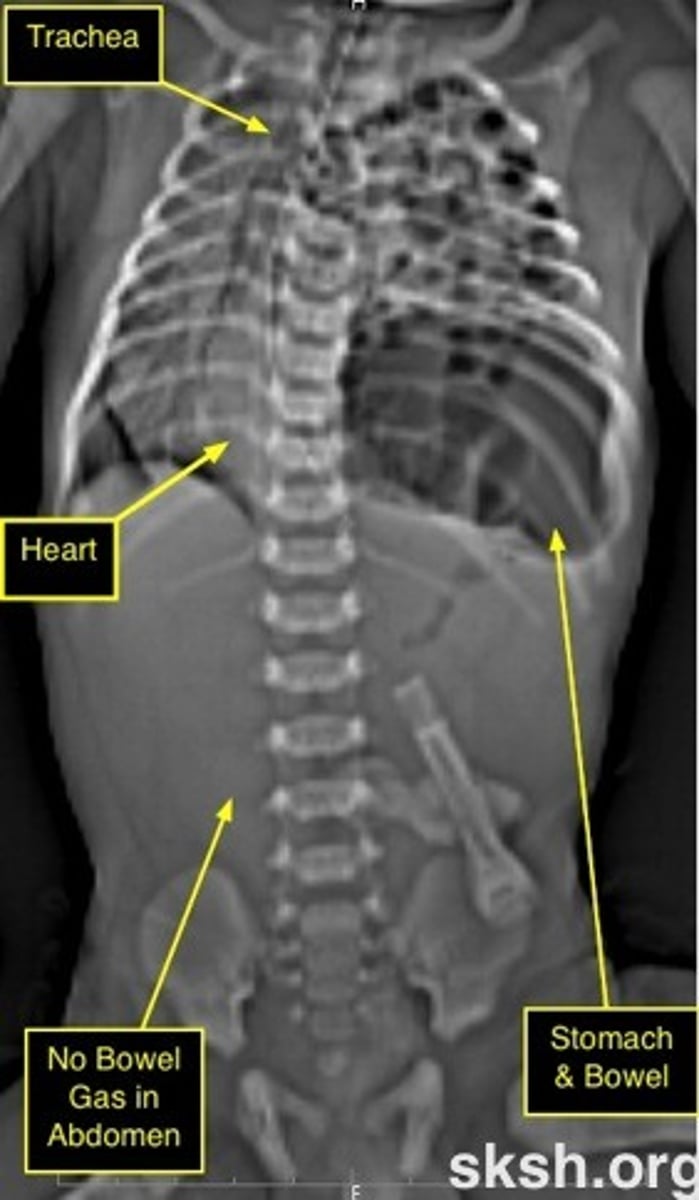

Newborn presents with respiratory distress barrel-shaped chest, absent breath sounds on the left, fair aeration on the right, scaphoid abdomen. Dx. Management.

Congenital diaphragmatic hernia (CHD)

- pulmonary hypoplasia

- pulmonary HTN

- 85% cases on the left abdominal viscera herniate into chest

- concave abdomen + barrel chest

- ER endotracheal intubation + gastric tube decompress stomach and bowel